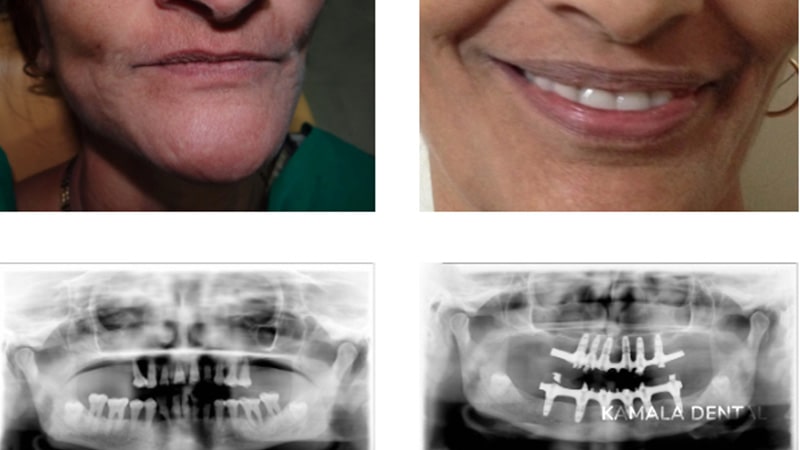

All-on-Four Implants

A full arch of teeth can be supported on just four implants strategically placed in the jaw. All-on-4 treatment is ideal for patients missing all their teeth, offering a fixed, natural-looking restoration in a shorter timeframe.